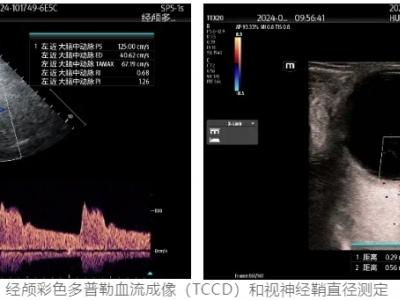

【健康科普】创伤性颅脑损伤(TBI)的床旁脑监测